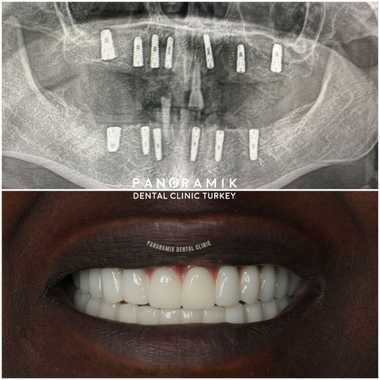

• Smile Time: Your smile will last for years with your teeth that have been used carefully and carefully and whose controls have not been interrupted. Take a look at our Before and after pictures.

In order to apply fixed prosthesis in edentulous patients, 7-10 implants are needed in the upper jaw and 5-7 implants in the lower jaw. In general, 8 implants are applied to the upper jaw and 6 implants to the lower jaw.